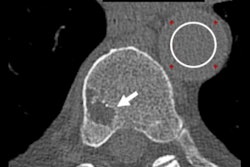

The investigators scanned a 40-cm water phantom and Sun Nuclear's Gammex multienergy phantom with both the photon-counting prototype and the conventional scanner, comparing both counting and spectral images. The photon-counting CT device produced images with 20% to 25% reduced noise compared to conventional CT and had higher spatial resolution, from 0.60 lp/mm for conventional CT to 0.69 lp/mm for the photon-counting device.